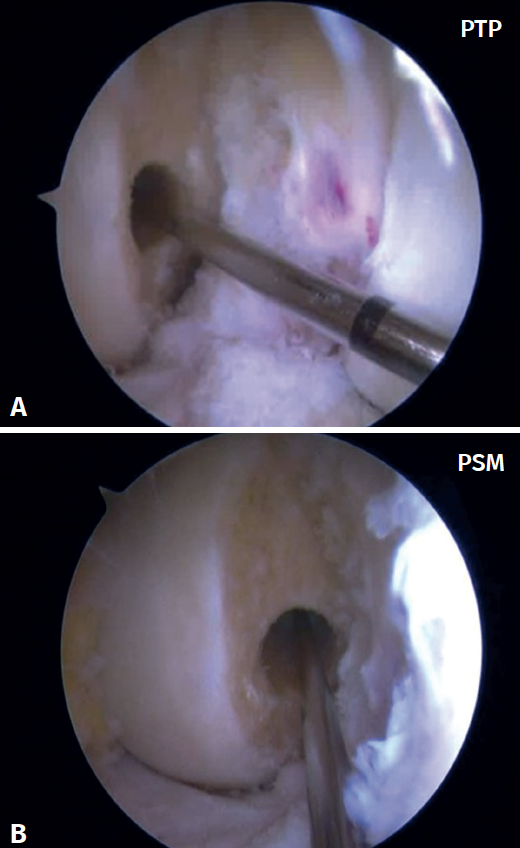

Pueden ser necesarios portales accesorios que permitan una visualización completa de la zona en la que deben realizarse los túneles femoral y tibial, ya que pueden proporcionar información adicional útil. Habitualmente, se utiliza el portal superomedial (PSM) a nivel parapatelar interno, pero también se pueden considerar otros portales, como el transpatelar (PTP), como podemos ver en las Figuras 1A y 1B. Por lo que sabemos, no existen descripciones comparativas previas con respecto a la posición del TF, teniendo en cuenta si el portal de visualización utilizado fue el PTP o el PSM.

Las referencias anatómicas para el portal de artroscopia de rodilla PSM implican el posicionamiento del portal por encima y ligeramente medial al borde medial de la rótula a lo largo de la línea articular. Sin embargo, para el PTP el portal se coloca estratégicamente a través del tendón rotuliano en el espacio intercondíleo, lo que proporciona una visualización frontal, ya sea centralmente o a lo largo del tendón rotuliano, y se coloca dentro del espacio intercondíleo, entre los cóndilos femorales. La visualización artroscópica del cóndilo femoral desde el PTP puede verse en la Figura 3A. La visualización artroscópica del cóndilo femoral desde el PSM puede verse en la Figura 3B.